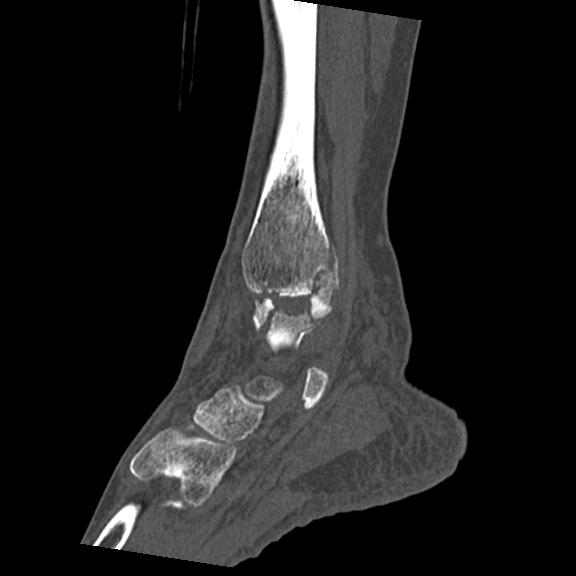

56476 8/28 4R 1/21 2R 左足関節 デジカメ写真 72歳女性 右足関節AS